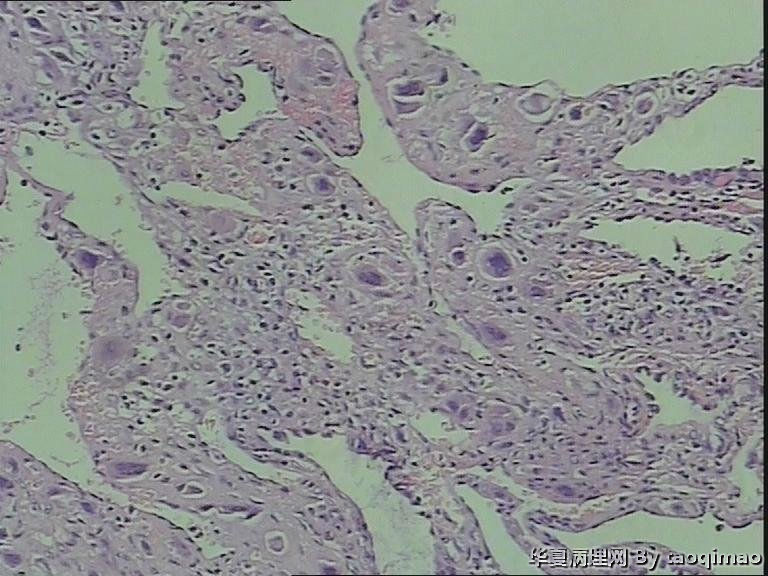

• 功血,滋养细胞浅肌层?图2

图2

这是患者第一次刮宫的内膜,怎么出报告呢

追问病史 除外绒癌 侵袭性葡萄胎

上一组图是全子宫切除后宫内膜及浅肌层的切片,取材时发现在子底及后壁有暗紫色血凝块与宫内膜分界不清

患者资料:39岁女,阴道不规则出血,2011,6,诊刮可见:内膜腺体囊性增生,现再次出血诊刮术。术中子宫后位,宫深9cm,子宫增大内膜不平,刮出内膜组织约2g。红褐色破碎组织一堆大小3X2.5cm,质软。